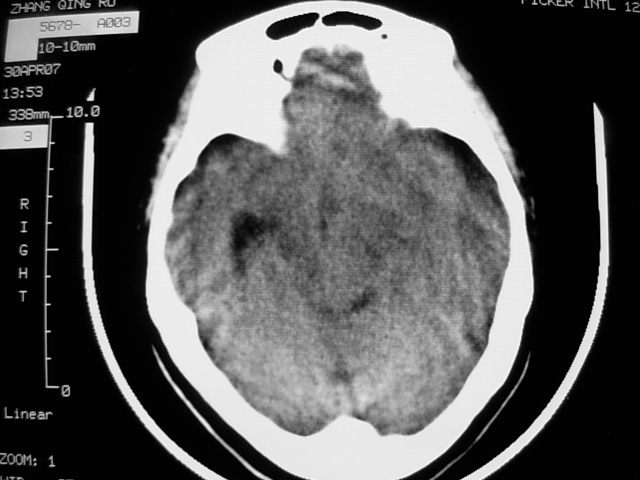

f39y,头疼、眩晕。患者拒绝强化。

左额叶见一巨大椭圆形略低、低密度混杂密度肿块,边界清楚,似与侧脑室额角相通,明显占位效应,左侧侧脑室受压变形,右侧侧脑室扩大,中线结构向右明显弧形移位。鞍上池闭塞。

考虑:1、左额叶良性占位性病变,以皮样囊肿可能性大,伴镰下疝。

肿瘤不再脑室内,左侧的脑室受压了;从平扫考虑两种可能:1.脑膜瘤;2.囊型胶质瘤。

病灶前外侧似可见软组织密度影,考虑囊性星形细胞瘤,建议增强或mr.